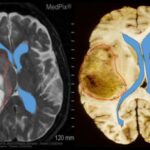

Malattie autoimmuni-Immagine: una citochina (blu) secreta dalle cellule T (rosso) stimola i monociti (sfondo) a nutrirsi delle ife di C. albicans (giallo). Credito: Luo Yu/Leibniz-HKI-